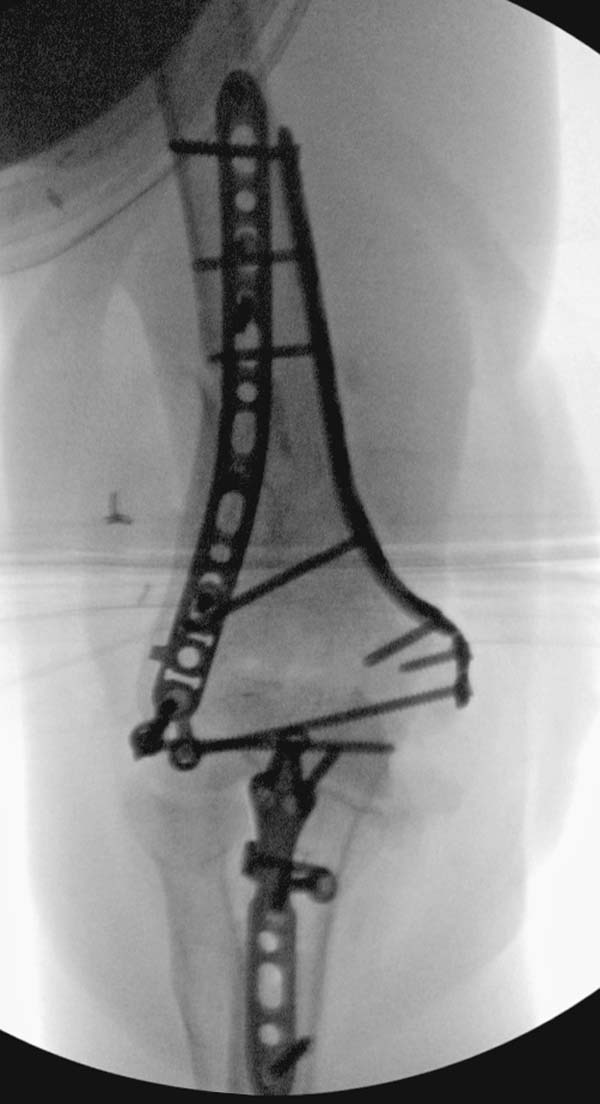

остаться до конца лечения, начал изучать язык... Для облегчения

транспортировки на второй день после поступления правая сторона была

фиксирована ретроградным гвоздем.

Теперь по серьезному. Учитывая качество кости и низкий гемоглобин,

периодический гемодиализ и воодушевленный результатом выступлении

Челнокова, вместо пластины решил попробовать гвоздь. Но жесткие FDА

условии не позволяют воспользоваться дивайсом до получения разрешения на

пользование.

Гвоздь из ретроградного гвоздя DePuy в 15 мм получился немного тоньше,

чем у Российских коллег.

Операция не обошлась без казуса, при подготовке гвоздя произошла ошибка

в расчете. Пришлось коррегигировать по ходу операции, где длинный

дистальный отдел гвоздя срезали во время операции.